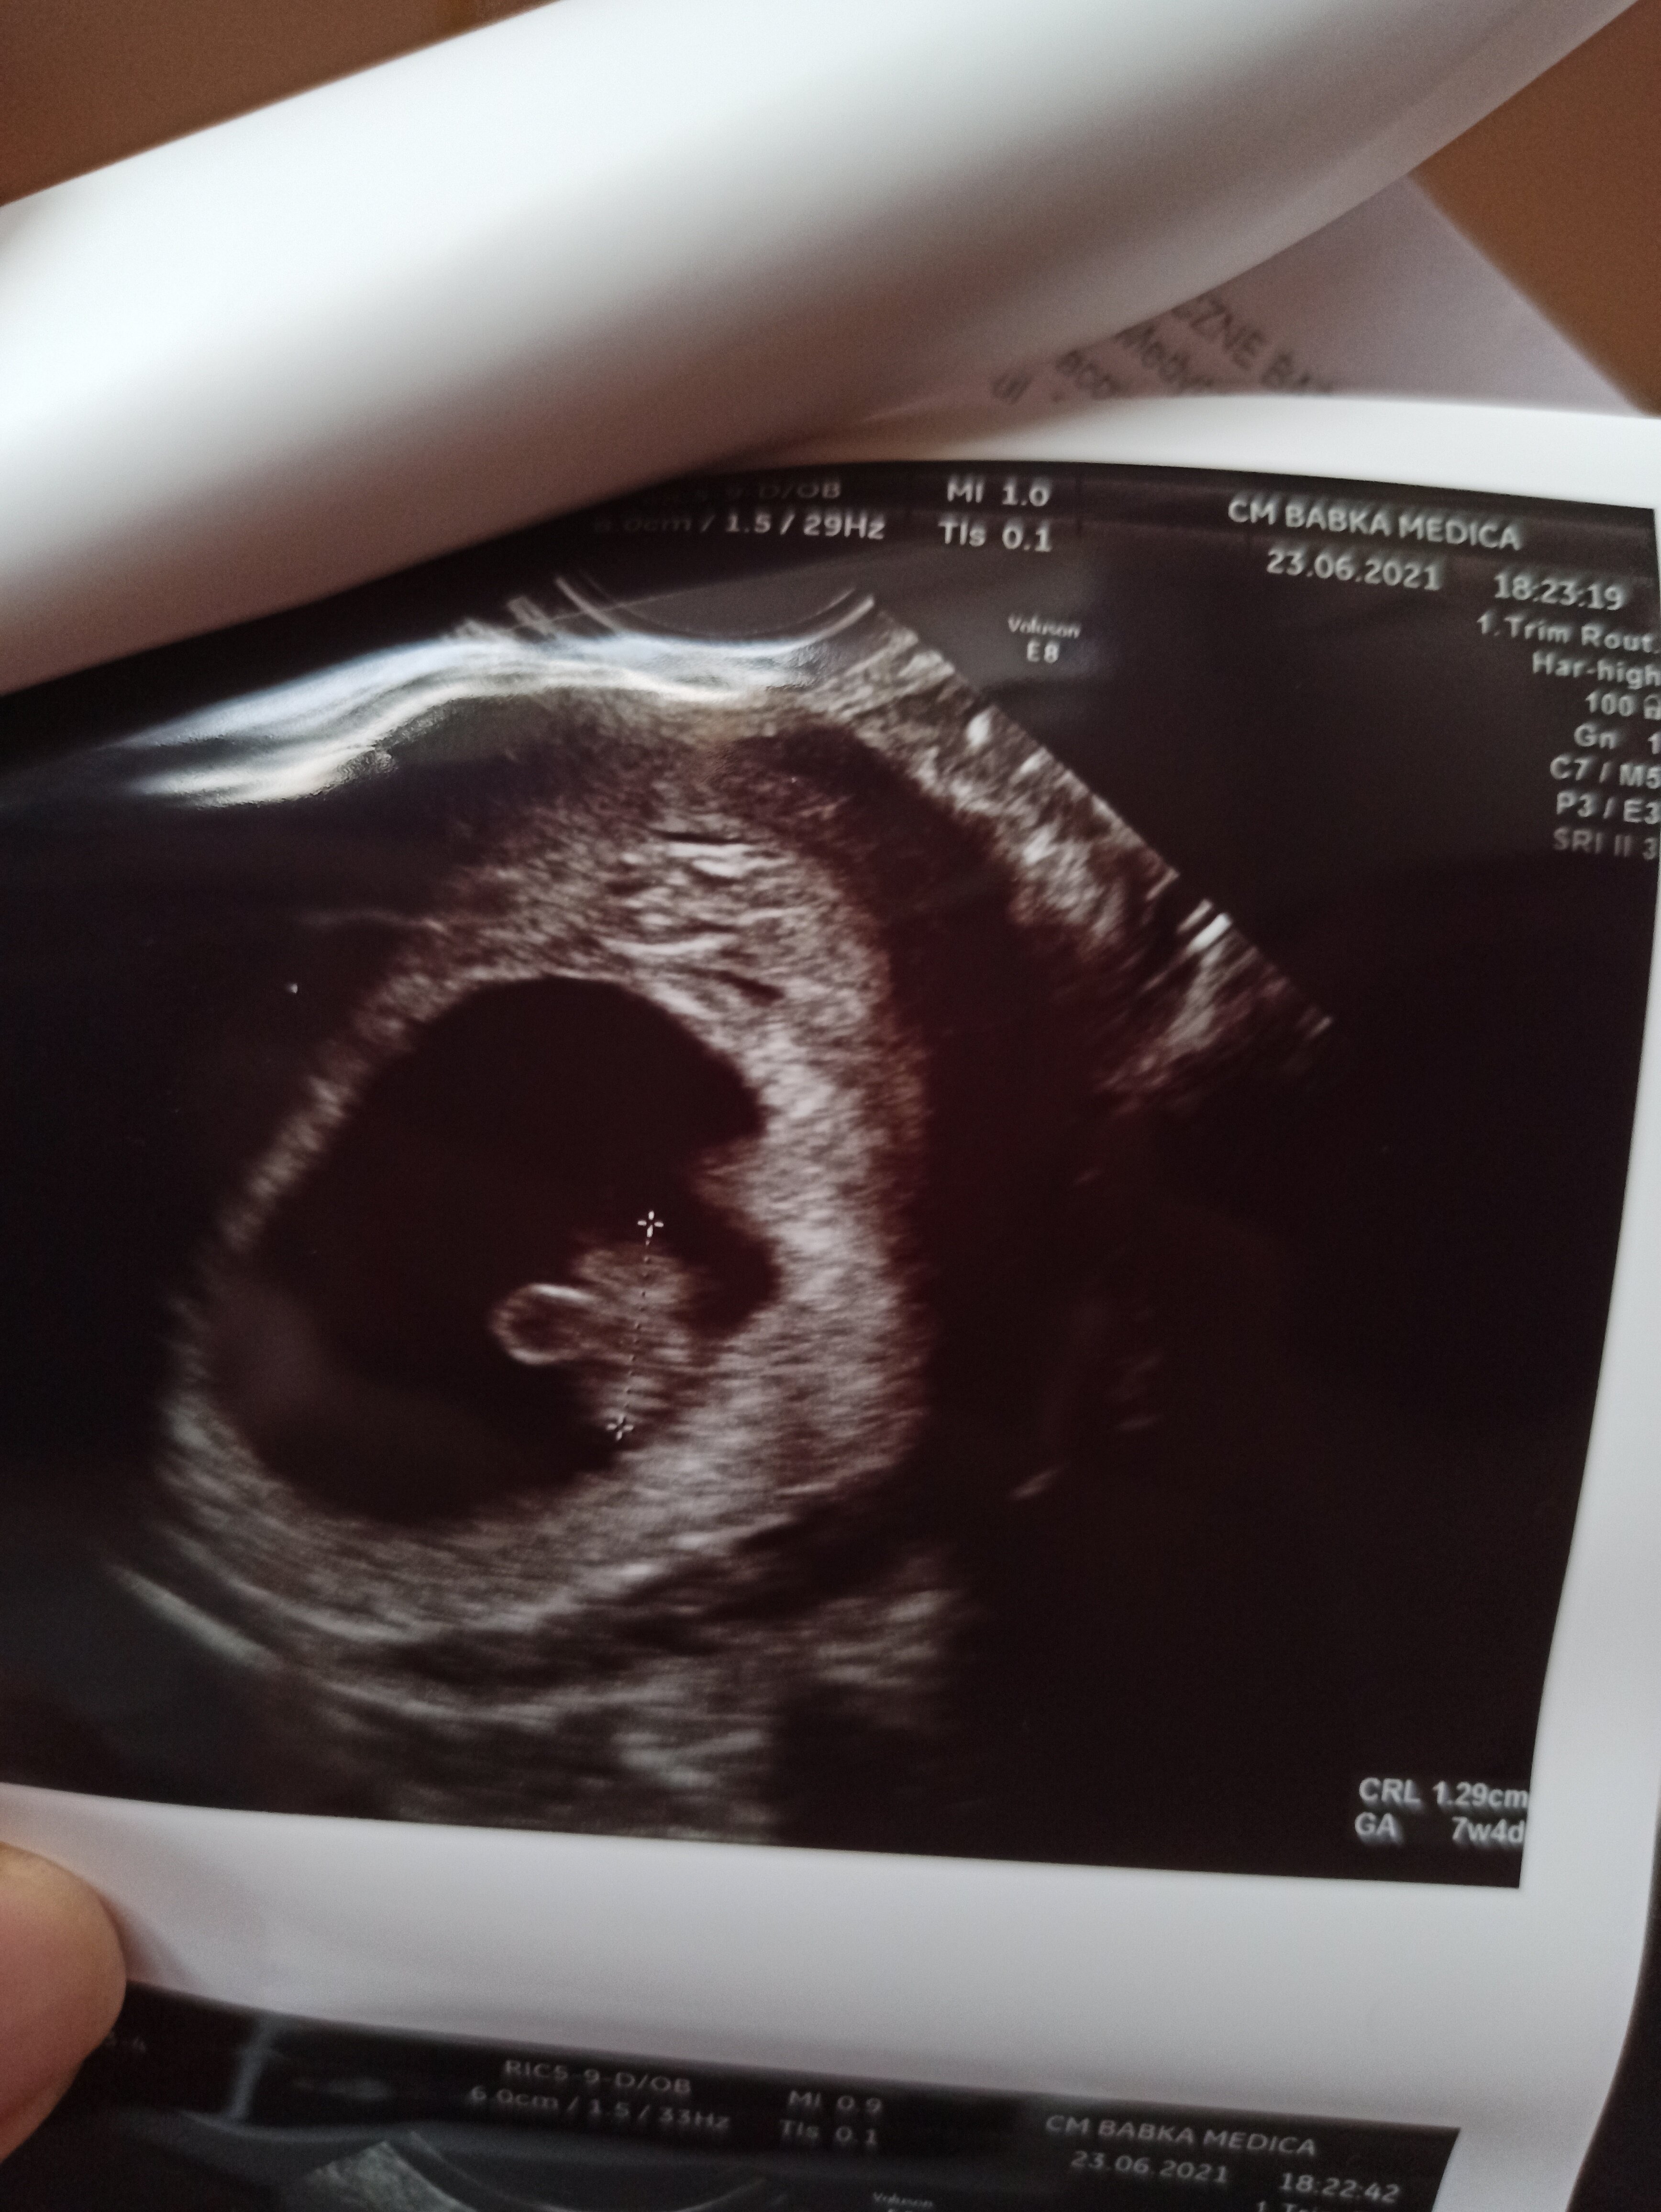

Ja miałam do tej pory 2 USG na przestrzeni 2 tygodni - pierwsze prywatnie i było super widać pęcherzyk i zarodek obok, do tego dodatkowy ekran przede mną, żebym wszystko widziała. Drugie USG 8+6 w Luxmed, nie dość, że okropna baba, to jeszcze nie miałam nawet jak spojrzeć na ekran, trwało to chwilę i dostałam tylko wydruki - zdjęcia jak dla mnie przypomniały chomika, żadnych kształtów dziecka. Straszna jakość. Teraz na prenatalne też pójdę prywatnie, bo aż mi szkoda tamtej wizyty, Luxmed chyba nadaje się głównie do robienia badań z pakietu

• IMG_20210623_202022.jpg

IMG_20210623_202022.jpg

1,6 MB · Wyświetleń: 74